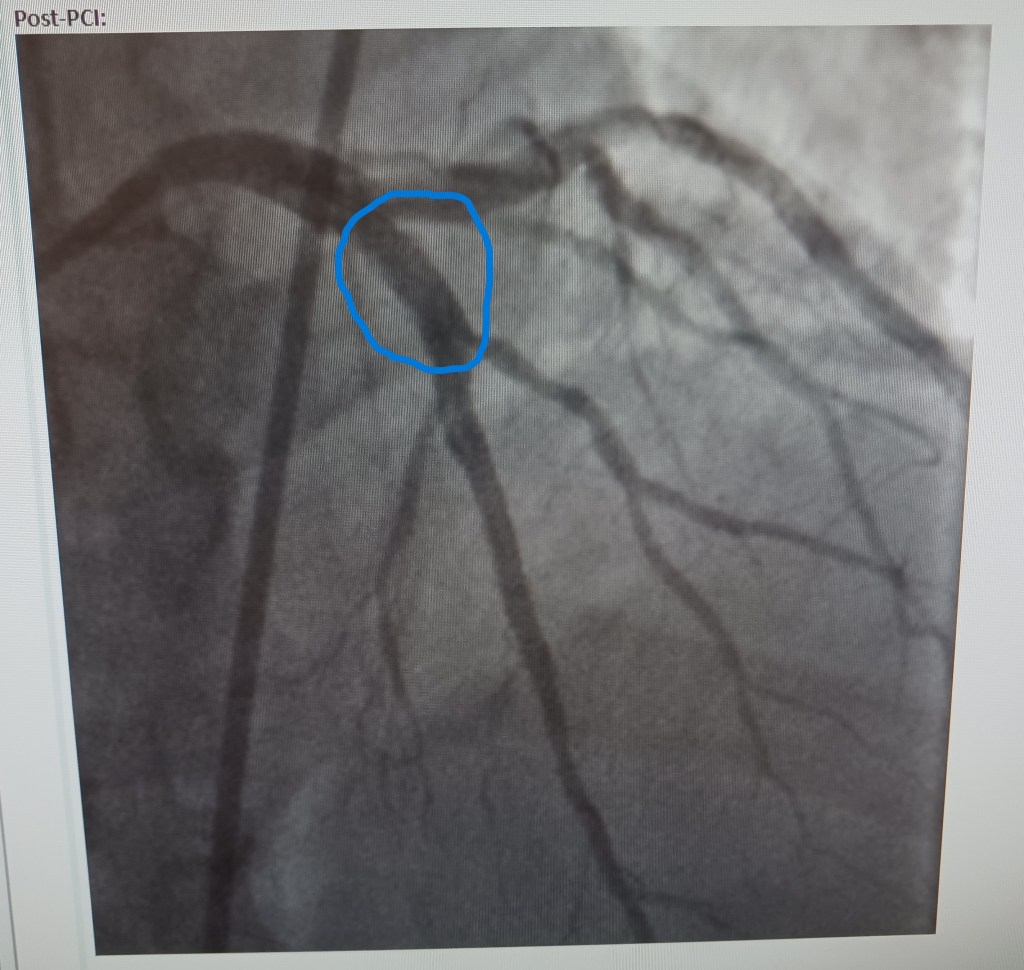

But that was 2023. I would shortly learn that I had developed a 100% blockage in my “widow maker” artery. At the time I was running the SF half that year, I had no clue. But I should have known. What I didn’t know was that the blockage was likely well above 80% and was getting ready to close. But there was no chest pain, which is the warning sign that something serious is about to happen. Then again, my cardiologist didn’t know either because was not feeling pain.

My cardiologist and I agreed that it was time for drastic measures to deal with the arrhythmia: an ablation procedure. But then the events of September of 2023 happened, and we had to prevent a serious or fatal myocardial infarction from possibly ending my life. Luckily, we got that fixed just in time.